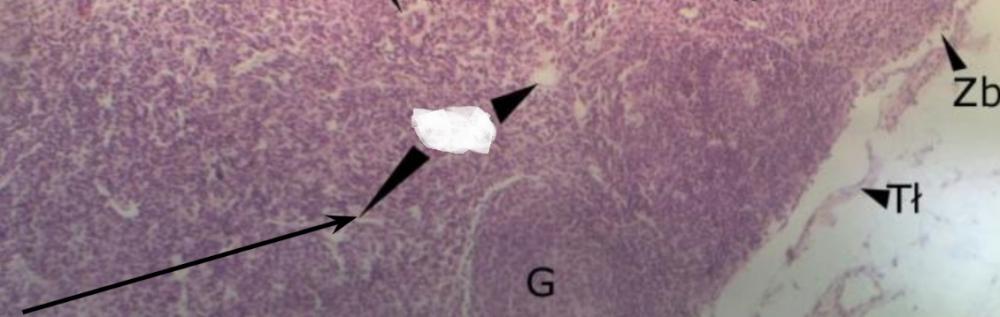

Pytanie 114

zatoka właściwa (śledziona)

Pytanie 115

nabłonek wielowarstwowy płaski (migdałek podniebienny)